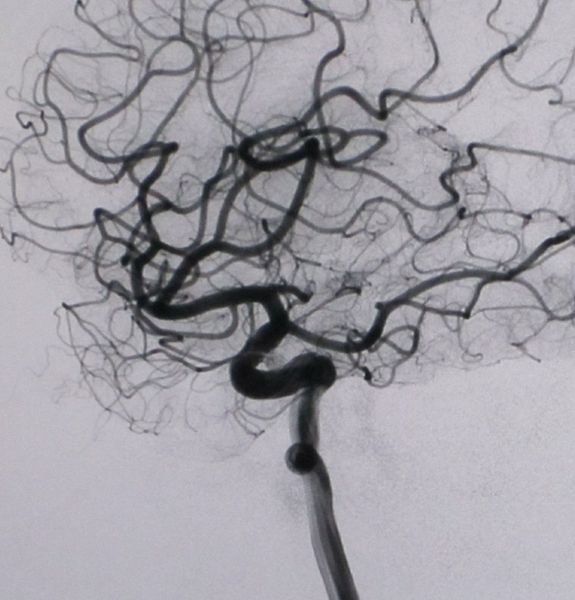

超选择性血管造影主要用于颅内肿瘤、脓肿、血肿、动脉瘤、动静脉畸形、动脉阻塞性病变以及颅脑外伤后等的诊断和定位。近年来由于采用了数字减影血管造影(DSA)技术,血管造影已经成为临床的一种重要的诊断方法,尤其在介入治疗中起着不可替代的作用。血管造影在头颈部及中枢神经系统疾病、心脏大血管疾病、及肿瘤和外周血管疾病的诊断和治疗中都发挥着重要作用。

DSA的成像基本原理是将受检部位没有注入造影剂和注入造影剂后的血管造影X线荧光图像,分别经影像增强器增益后,再用高分辨率的电视摄像管扫描,将图像分割成许多的小方格,做成矩阵化,形成由小方格中的像素所组成的视频图像,经对数增幅和模/数转换为不同数值的数字,形成数字图像并分别存储起来,然后输入电子计算机处理并将两幅图像的数字信息相减,获得的不同数值的差值信号,再经对比度增强和数/模转换成普通的模拟信号,获得了去除骨骼、肌肉和其它软组织,只留下单纯血管影像的减影图像,通过显示器显示出来。

通过DSA处理的图像,使血管的影像更为清晰,在进行介入手术时更为安全。

DSA的成像方式分为静脉注射数字减影血管造影(IVDSA)及动脉注射数字减影血管造影(IADSA)。前者指经静脉途径置入导管或套管针注射对比剂行DSA检查,可分为非选择性IVDSA即导管置入外周静脉或上腔静脉内显示动脉影像,及选择性IVDSA即导管头置于受检静脉或心腔内注射对比剂显影。后者也可分为非选择性动脉造影及选择性动脉造影。非选择性IADSA是指经动脉途径穿刺插管后,将导管头端置于靶动脉的主动脉近端注射对比剂作顺行显影;而选择性IADSA是指将导管头端进一步深入到靶动脉的主干或主干的分支内进行造影。

(1) 颅内及颈部血管性疾病。如动脉粥样硬化、栓塞、狭窄、闭塞性疾病、动脉病、动静脉畸形、主动脉瘤的形态、动静脉瘘等,其诊断灵敏度、特异性和正确性都很高达95—100%。颅内占位性病变,如颅内肿瘤、脓肿、囊肿、血肿等及颅脑外伤所致各种脑外血肿。